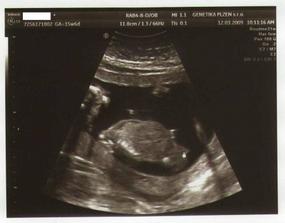

11.3.09 - KO dopadla výborně, miminko opět v akci,všechny orgány OK, srdíčko tluče

12.3.09 - AMNIO na Genetice v Plzni- nic příjemnýho, ale vydržet se to dalo, viděli jsme s tatínkem všechny orgány podrobně a hlavně: už víme pohlaví našeho vytouženého miminka:

je to HOLČIČKA !!!